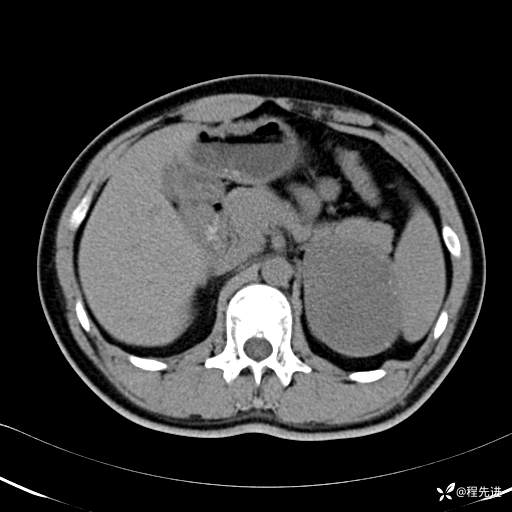

CT平扫:(CT值:平扫,27HU,动脉期,27HU,门静脉期,31HU,平衡期,32HU)

CT增强:

动脉期:

门静脉期: